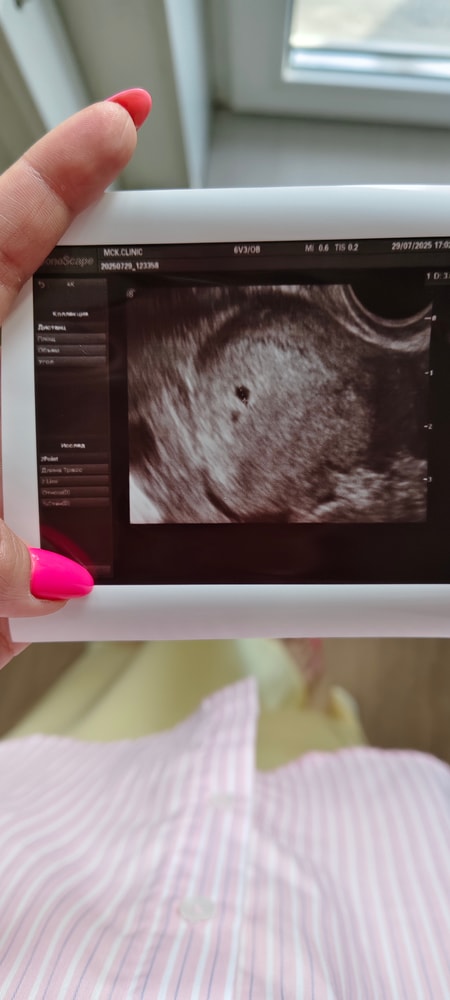

Супер 💕🥲после завтра тоже иду на узи первое ... 5 недель и 1 день будет... Надеюсь тоже найдем крошку

Алена, да, от 1000 уже должны увидеть плодное яичко)